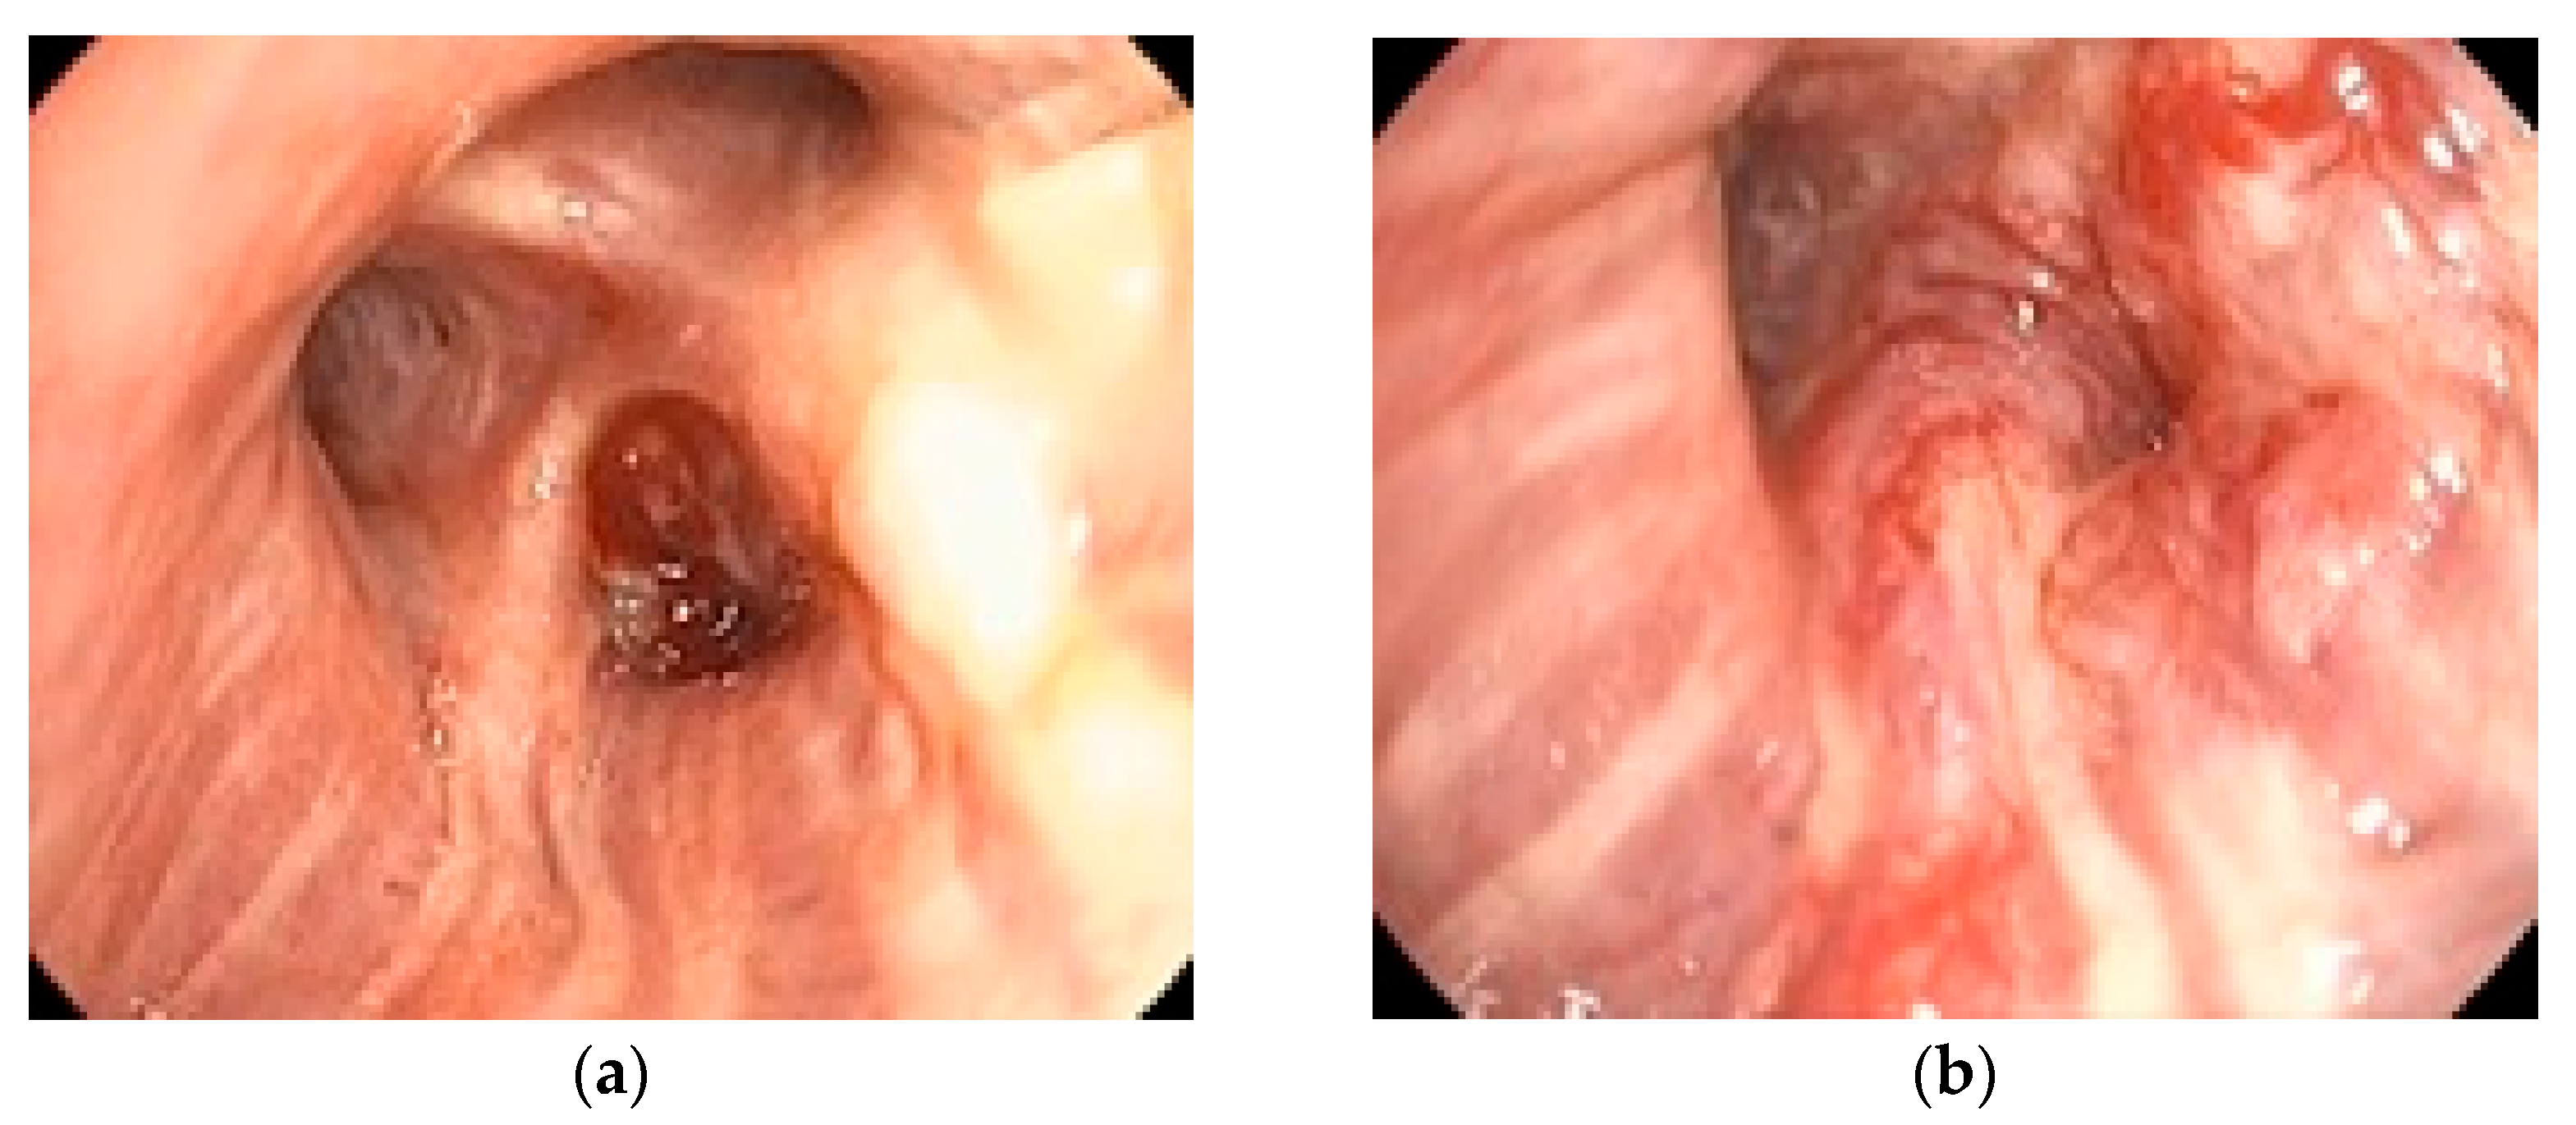

All patients (100%) underwent bronchoscopy, while EBUS-TBNA was performed in 42 patients (62.7%) with mediastinal lymphadenopathy detected on imaging. No significant complications related to either procedure were reported, confirming the safety of the proposed algorithm. Figure 1 illustrates a representative bronchoscopic finding in a 72-year-old ex-smoker male with an adenocarcinoma of the dorsal segment of the right upper lobe, showing well-vascularized tissue with distal bronchial invasion and significant stenosis due to extrinsic compression and mucosal infiltration. Figure 2 depicts an EBUS-TBNA procedure in a 69-year-old ex-smoker male without endobronchial tumor expression, performed under local anesthesia and mild sedation at station 4R, with a final diagnosis of small cell carcinoma confirmed by immunohistochemistry (thyroid transcription factor-1 (TTF1) positive, synaptophysin (SYN) positive, Ki67 proliferation index 98%).

Figure 2. EBUS-TBNA image (institutional archive).